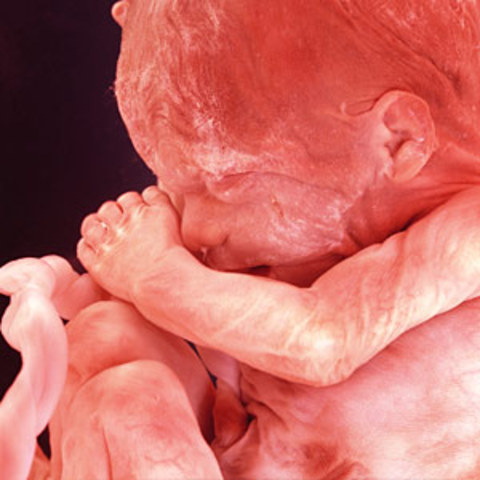

• 9 month - due date

The fetus reaches full growth. It measures 14-15 inches from head to buttocks and weighs 6-8 pounds. During this last month, the baby acquires antibodies from its mother which will give it temporary immunity againsta some diseases. The eyes are normally blue at birth because pigmentation is not normally formed untilafter a few weeks of exposure to light. Vernix is present over the entire body. The fetus will alternate between periods of activity and periods of quiet.